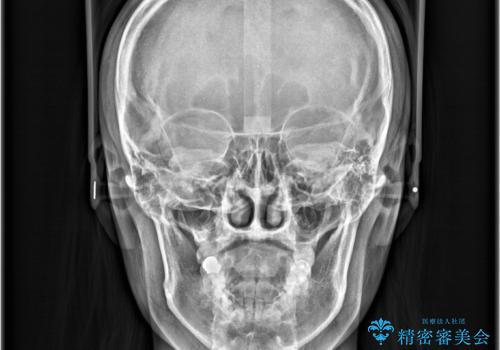

- 歯の捻じれやデコボコを主訴にご来院された患者様です。

矯正治療の精密検査を行った結果、非抜歯(歯を抜かない)矯正治療を選択いたしました。

本症例では、治療の途中で**バイトアップ(咬み合わせを一時的に挙上する処置)**を行い、

上下の歯が干渉しない環境を作りながら、捻転や叢生の改善を進めました。

これにより、歯を無理に動かすことなく、効率的かつ安全に歯列を整えることが可能となります。

その結果、約10ヵ月という比較的短期間で歯列と咬み合わせが整い、機能面・審美面ともに良好な結果を得ることができました。